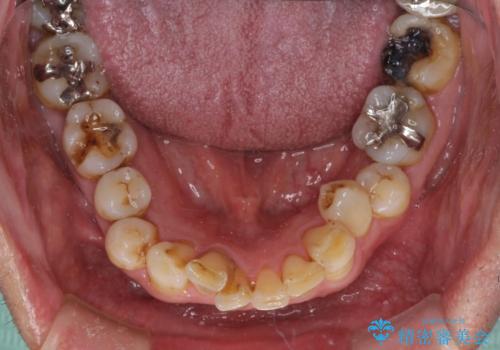

- 銀歯やインレーが外れたまま放置された奥歯の治療を希望して来院された患者様です。

咬合力が著しく強いため、欠損の多い歯はフルジルコニアクラウンへ、その他の虫歯はゴールドインレー(PGAインレー)にて修復することとしました。

来院時は全てセラミックでの治療を希望されていましたが、歯列や咬み合わせから咬合力による破損リスクが高いと判断されたため、ゴールドインレーを選択しました。